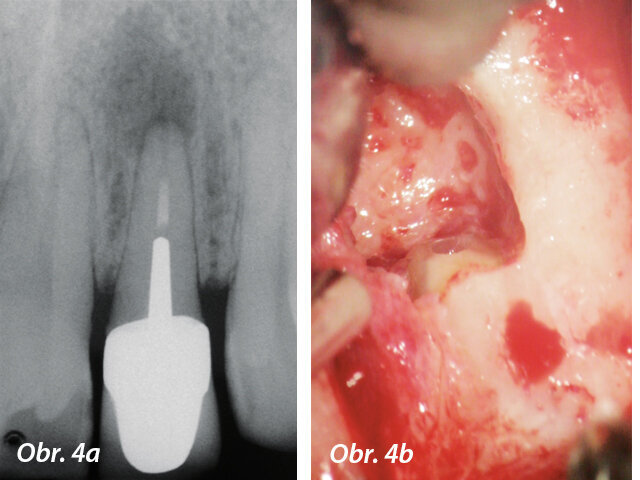

Apikální chirurgie

MTA má nejpříznivější výsledky jako materiál pro apikální chirurgii. Signifikantně vykazuje méně zánětlivých reakcí, podporuje tvorbu terciálního cementu a regeneraci periapikálních tkání (Torabinejad a Chivian 1999) (obr. 4a–f).

Předoperační RTG s velkým periradikulárním nálezem a periapikální chirurgie

Aplikace PD MAP White pomocí MAP systému a kondenzace MTA pluggerem

Pohled přes zrcátko - MTA výplň v apikální části a postoperační RTG s apikální výplní